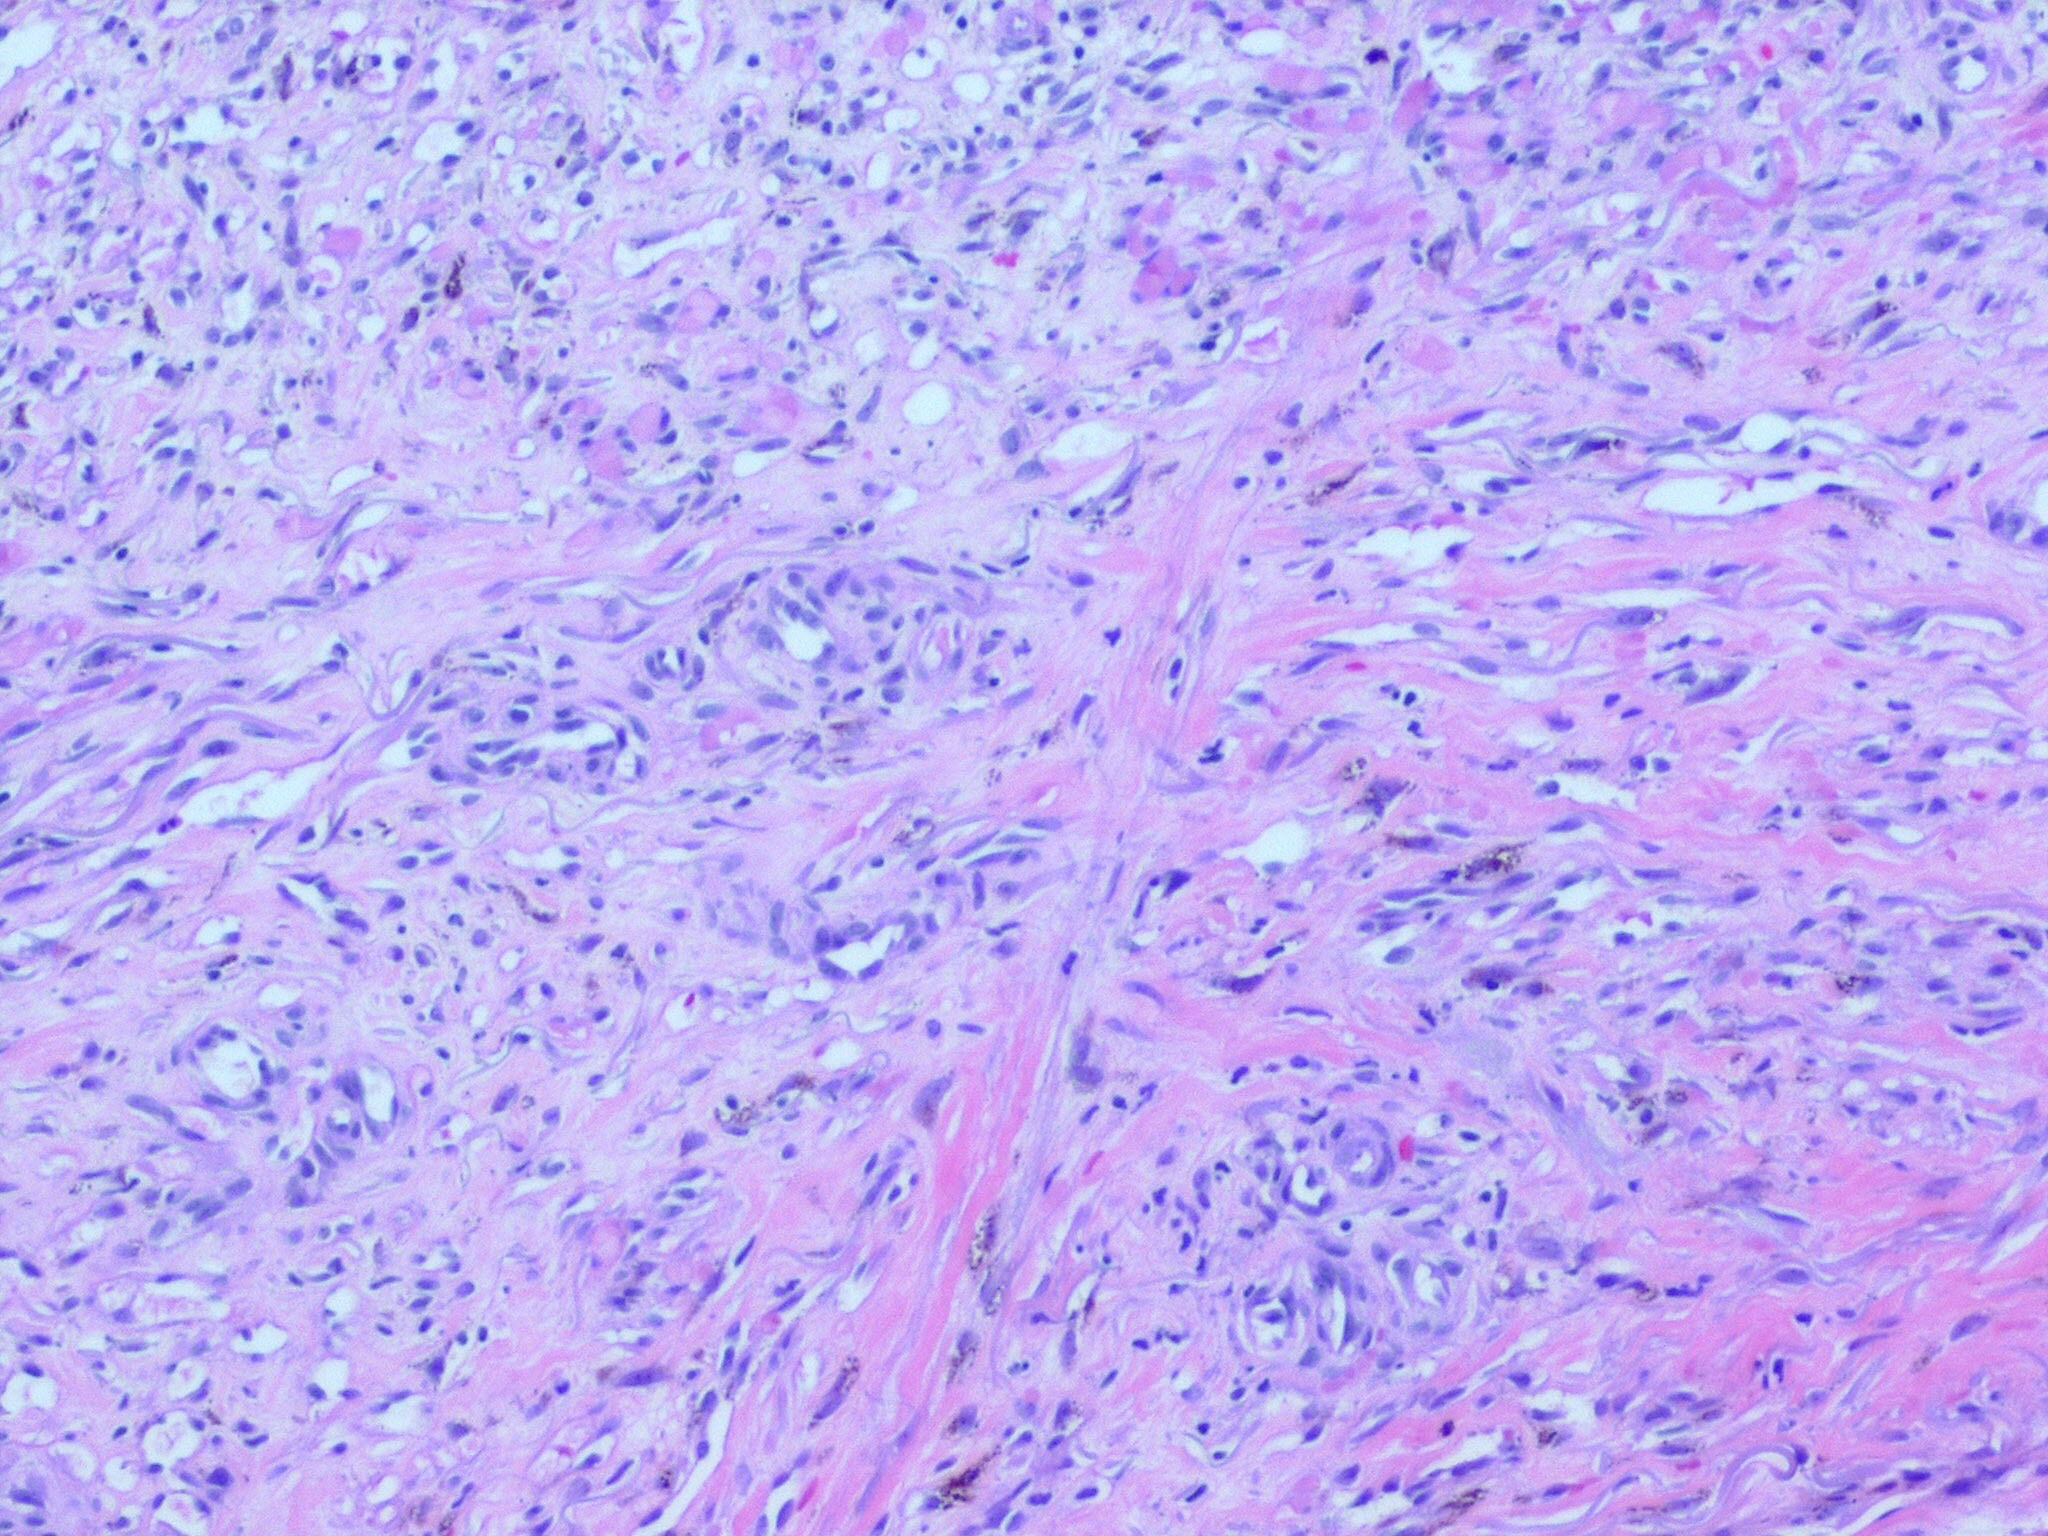

HISTOPATHOLOGY

The histopathology of KS is dependent on the stage of KS development. Early patch-like lesions exhibit rather discrete histopathologic changes, consisting mainly of an increase in the number of dermal vessels, outlined by slightly irregular endothelial cells (Fig. 128-5). These vessels, located mainly in the superficial dermis are parallel to the skin surface, are frequently slightly irregular, and may form bizarre slits and clefts. In the surrounding skin focal hemosiderin, deposits and extravasated erythrocytes can be found as well as a moderate inflammatory infiltrate. Important differential diagnoses of this stage include lymphangioma and granulation tissue.

The pathology of KS plaques is more characteristic and reveals extensive vascular proliferation at all levels of the dermis with multiple dilated and angulated vascular spaces dissecting the collagen leaving a spongy network of collagen tissue. A characteristic sign of KS papules is the presence of solid cords and fascicles of spindle cells arranged between the jagged vascular channels. This biphasic angiomatous and solid tumor morphology changes to a clear-cut sarcomatous morphology with progression of the disease.

Nodular lesions consist predominantly of spindle cells arranged in bundles and interlacing fascicles and interspersed, irregular, slit-like vascular spaces without endothelial linings. Advanced lesions may display pronounced pleomorphism, nuclear atypia, and mitotic figures. At the periphery of solid tumors, (lymph) angiomatous-like portions of KS with bizarre vascular lumina and intravascular and extravasated erythrocytes, as well as siderophages, may be preserved. Erythrocytes, which appear as eosinophilic globules, are trapped within the slits and clefts formed by the spindle cells and erythrophagocytosis are occasionally observed. As in all other stages of KS, a moderate inflammatory infiltrate consisting of lymphocytes, histiocytes, plasma cells, and, sporadically, neutrophils is regularly present.